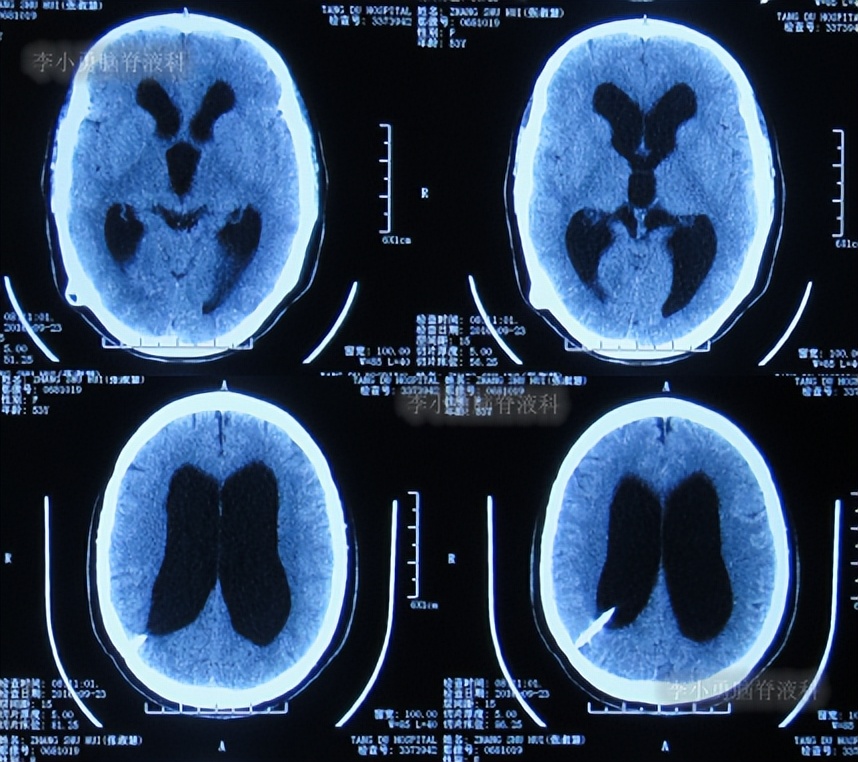

住院后3天即2016年8月19日,查头颅CT:幕上脑室扩张( 图-9 )。

图-9: 2016年8月19日头颅CT

第3次出院后21天即2016年9月23日,复查头颅CT:幕上脑室仍扩张( 图-10 )。

图-10: 2016年9月23日头颅CT